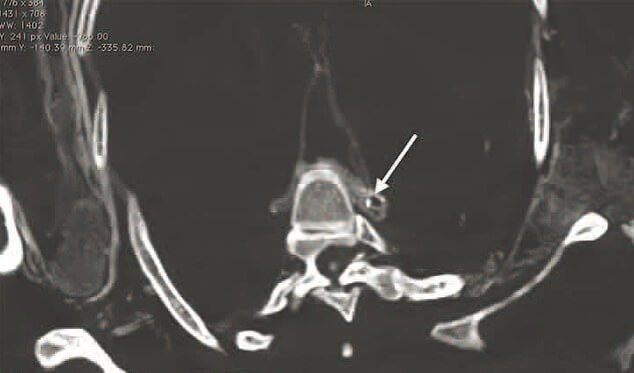

Изучив их тела при помощи компьютерного томографа исследователи обнаружили, что несмотря на правильное по сегодняшним меркам питание у мумий наблюдалось скопление жировых веществ в артериях. Из этого исследователи сделали вывод, что рыбная диета никак не может гарантировать сохранение артерий в идеальном состоянии.

Бляшка в брюшной полости мумии